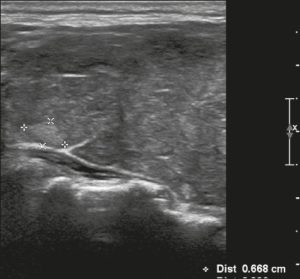

Ở đây, chúng tôi cung cấp các ví dụ minh họa việc áp dụng thực tế hệ thống ACR TI-RADS (Hình 18, 19, 20, 21). Các chú thích dưới hình mô tả chi tiết các mục đã được đánh giá và hiển thị điểm số trong ngoặc đơn.

Hình 19. Hình ảnh nhân giáp dạng đặc (2 điểm), giảm âm rất mạnh (3 điểm), rộng hơn cao (0 điểm), có bờ trơn láng (0 điểm), và không có các ổ tăng âm hay bóng lưng (0 điểm). Do đó, tổng điểm là 5 điểm và mức độ nguy cơ được phân loại là TR4.